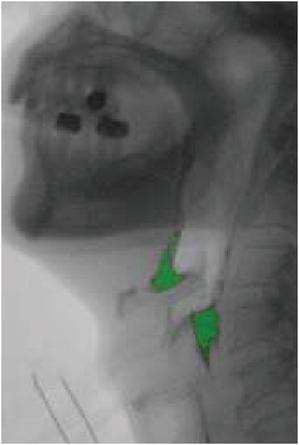

However different lighting conditions will lead to VFSS video image research, therefore, we need from a frame to use gaussian background model of gray image algorithm to adjust balance in the appeal of models, we the pixels by weighted gaussian mixture distribution model, results show that fluid of VFSS barium extraction has a certain impact. The picture shows the result. The background subtraction algorithm greatly improved the effect of body part shaking, and the accuracy of barium extraction was up to 85% (relative to the expert mark), which was significantly better than the results obtained by the frame difference algorithm alone, but the overall calculation time was improved.

images

Figure 6 Experimental results of barium extraction based on background subtraction.

Figure 7 Enlarged display of experimental results.

Fuzzy logic is a Boolean logic extension that deals with some real concepts. According to the conditions, we calculate the residual amount of the mouth, epiglottic cartilage and piriform fosse, and there will still be some noise influence. Therefore, when the pixel value of the system is not estimable, we default to 0 residual [26].